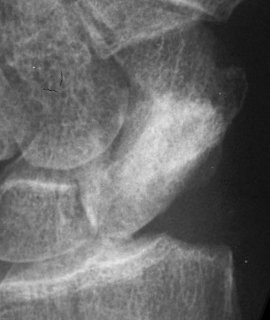

Case 6. A dorsal approach for this proximal pole fracture would have been a better choice.

Click for larger image